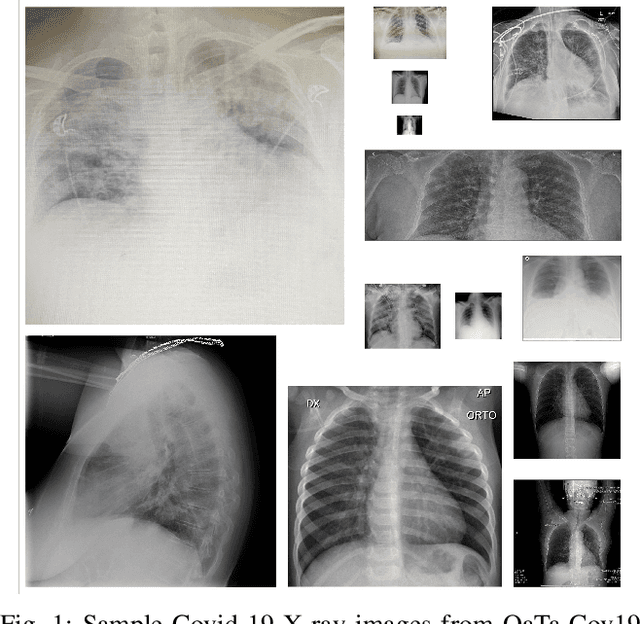

Coronavirus disease (Covid-19) has been the main agenda of the whole world since it came in sight in December 2019. It has already caused thousands of causalities and infected several millions worldwide. Any technological tool that can be provided to healthcare practitioners to save time, effort, and possibly lives has crucial importance. The main tools practitioners currently use to diagnose Covid-19 are Reverse Transcription-Polymerase Chain reaction (RT-PCR) and Computed Tomography (CT), which require significant time, resources and acknowledged experts. X-ray imaging is a common and easily accessible tool that has great potential for Covid-19 diagnosis. In this study, we propose a novel approach for Covid-19 recognition from chest X-ray images. Despite the importance of the problem, recent studies in this domain produced not so satisfactory results due to the limited datasets available for training. Recall that Deep Learning techniques can generally provide state-of-the-art performance in many classification tasks when trained properly over large datasets, such data scarcity can be a crucial obstacle when using them for Covid-19 detection. Alternative approaches such as representation-based classification (collaborative or sparse representation) might provide satisfactory performance with limited size datasets, but they generally fall short in performance or speed compared to Machine Learning methods. To address this deficiency, Convolution Support Estimation Network (CSEN) has recently been proposed as a bridge between model-based and Deep Learning approaches by providing a non-iterative real-time mapping from query sample to ideally sparse representation coefficient' support, which is critical information for class decision in representation based techniques.